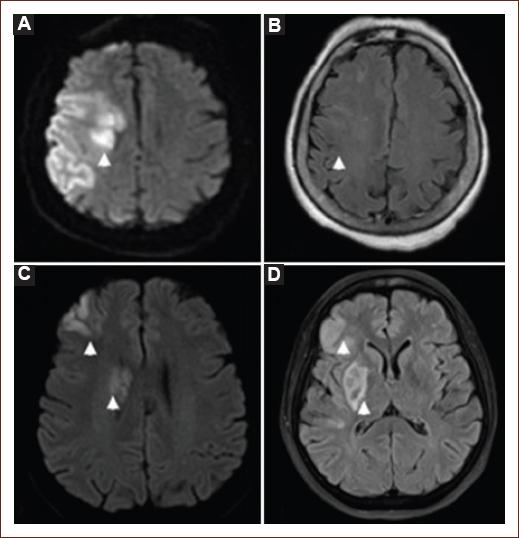

MRI can provide estimates of penumbral tissue through the combination of diffusion and perfusion imaging, but in practice, this is less available and more difficult to interpret. MRI sequences considered to be essential for AIS are apparent diffusion coefficient (ADC), DWI (ischemic findings appear from the 1st few min after symptom onset), susceptibility-weighted imaging (SWI, so as to detect any hemorrhage that may not be evident in other sequences), and FLAIR (ischemic changes will appear after 6 h from symptom onset). ADC is used in conjunction with DWI to distinguish truly ischemic lesions. DWI is highly sensible (88-100%), specific (95-100%), and accurate (95%) to detect and delimitate parenchyma at risk of infarction9. This sequence can demonstrate hyperintensities in oligemic tissue and may overestimate infarct size13, so information obtained with his method must be interpreted with caution. Lesion volume determined by DWI and its pattern seems to be related to collateral flow grade in AIS42. Supratentorial infarcts with a great volume (> 100 ml) are related to higher bleeding risk and lower possibilities of benefit from MT; those of intermediate size (70 - 100 ml) have an uncertain prognosis regarding reperfusion therapy43. MRI is more useful than NCCT to evaluate the posterior fossa and brainstem, as MRI presents no bone artifact. Both NCCT and MRI have distinct and clearly defined roles in decision-making. Figure 5A and B shows a DWI-FLAIR mismatch, while figure 5C-D shows no mismatch.

Figure 5 Magnetic resonance imaging in patients with acute ischemic stroke. Lesion shown on diffusion-weighted imaging (DWI) (A) but not on fluid attenuation inversion recovery (FLAIR) imaging (B); thus, it is considered a DWI-FLAIR mismatch. Meanwhile, the lesion on DWI (C) has a corresponding parenchymal hyperintensity on FLAIR (D), so there is no mismatch.